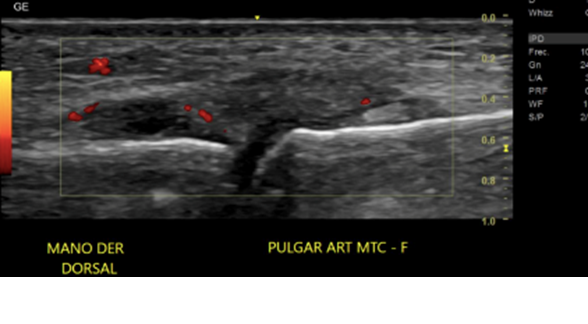

• A nivel de art MTCF dorsal del pulgar se obs proliferación sinovial con señal al Doppler- sugerente sinovitis.

• LCC engrosado a nivel de art MTCF, hipoecogénico con señal al Doppler, se obs solución de continuidad que se acentúa a la maniobra dinámica, con aponeurosis del aductor interpuesto en este sugerente de lesión de Stener.